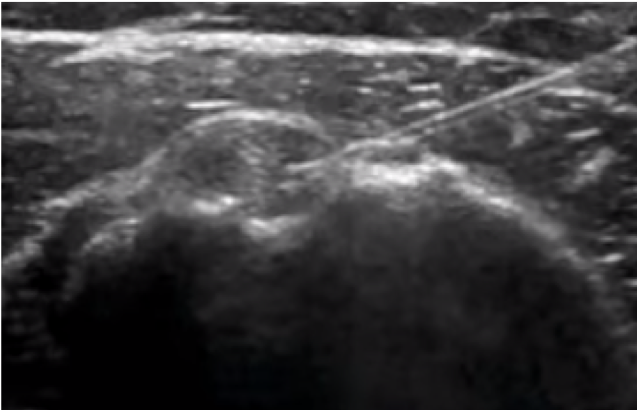

Bicipital tendinitis is a condition caused by inflammation of the long head of the biceps muscle’s tendon. It’s commonly caused by sudden overuse of the muscle and rotator cuff pathology such as muscle or tendon tears, chronic impingement, multidirectional shoulder instability, calcifications, and deconditioning. Signs in physical examination correlating with bicipital tendinitis are pain at the bicipital groove and a positive provocative test such as Speed’s test and Yergason’s test, although studies have shown that their sensitivity might be poor.1